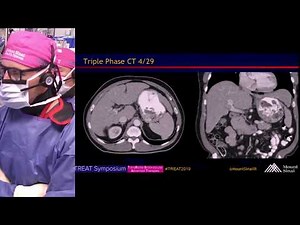

Y-90 Radioembolization Workup …